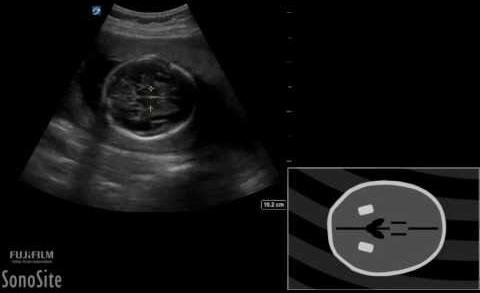

Ultrasound CRL Differences Key in Predicting sIUGR in MCDA Twins

In a recent study published in BMC Pregnancy and Childbirth,…